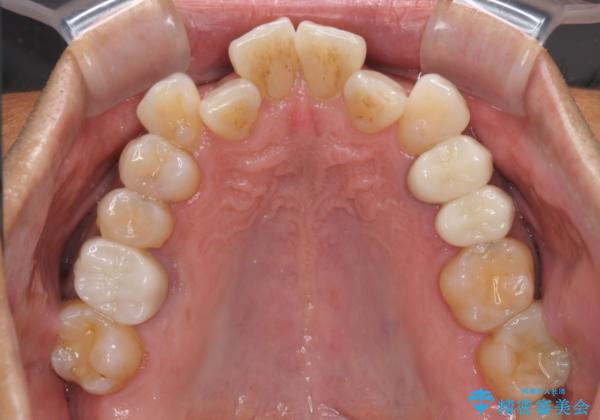

- 2年ほど放置していた左上の仮歯がとれたことをきっかけにご来院された患者様です。

セラミック治療がご希望でしたが、ときどき歯肉が腫れるということで根管治療もご希望されました。

左上で効果を実感して頂き、その後右上もご希望されました。合計3本の歯を治療しました。

左上の仮歯を2年使用して穴があいて外れたことをきっかけにご来院されました。

レントゲン上からも、歯の中(根管)が汚れている可能性があることをご説明したところ、根管治療からやり直しをすることになりました。

腫れもなくなり、見た目もきれいになったため、右上もご希望されて計3本の歯を治療しました。患者様には大変満足して頂きました。